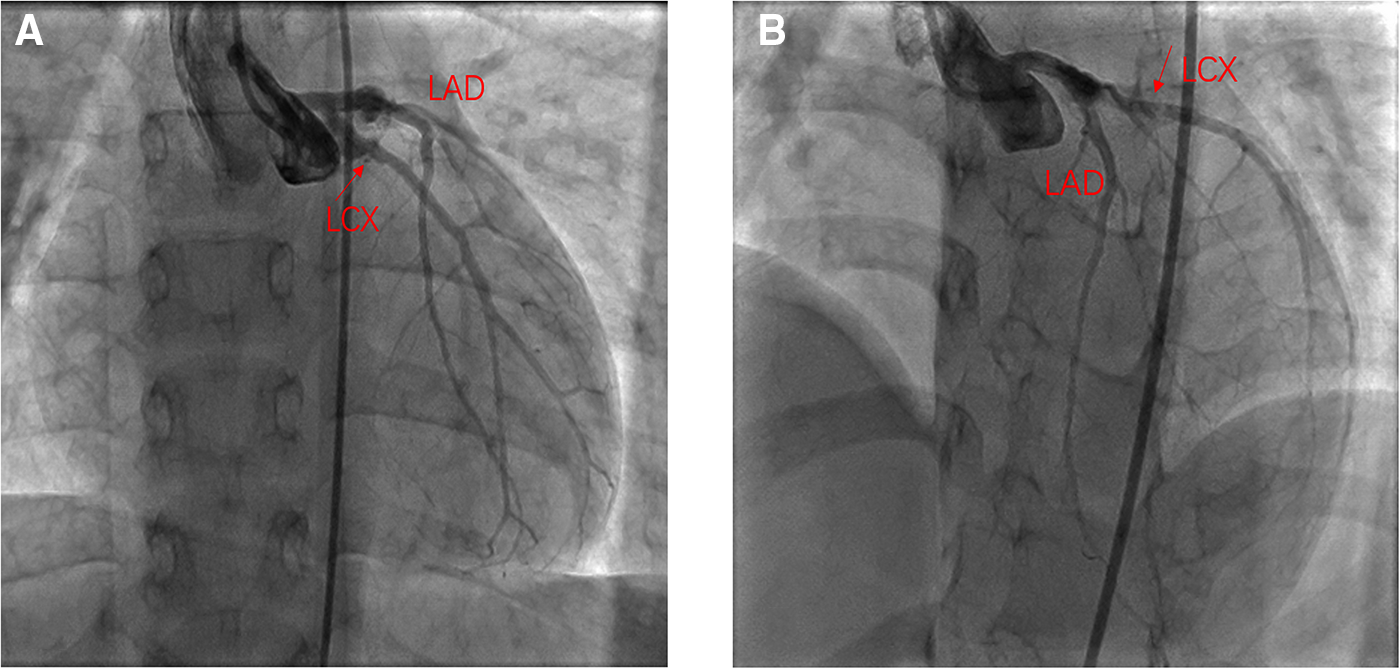

Figure 3

One year after the PCI angiography showed good flow in the LCX. (A) Angiography in right anterior oblique15° and Caudal 15°; (B) Angiography in left anterior oblique 45° and Cranial 25°.